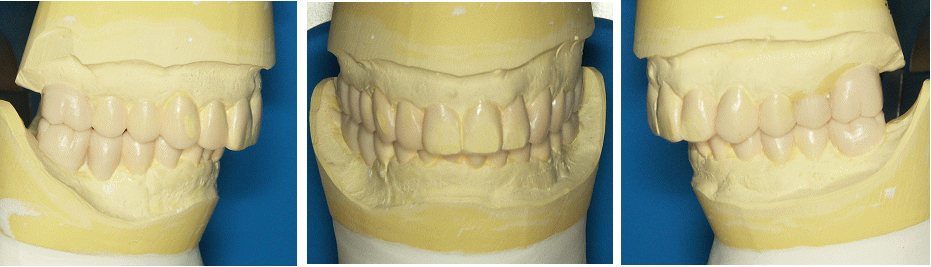

シュミレーションと治療計画の決定

治療のゴールを蝋細工(ワックスアップ)でイメージ化します。この工程により必要な治療のオプション(外科処置、補綴処置、歯周処置、矯正処置、インプラント処置など、、、)が明らかになり、細部にわたる治療計画を決定し契約になります。複雑な治療になるほど省いてはならない大切な工程です。 |